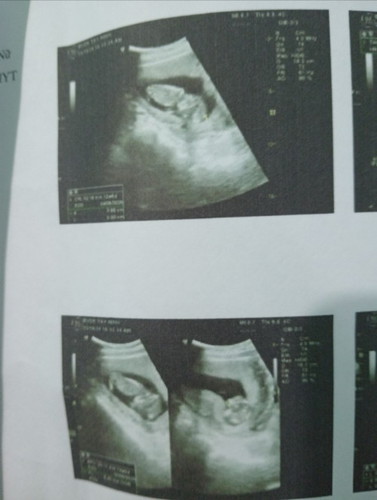

Mọi người ơi cho em hỏi e đc 15tuần mà con em đc 63gram vậy đủ tiêu chuẩn chưa mn. Cho em xin ý kiến